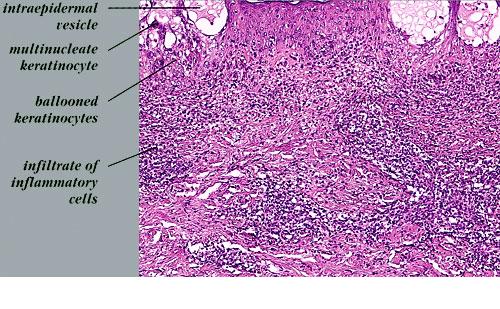

Herpes simplex = العقبول البسيط